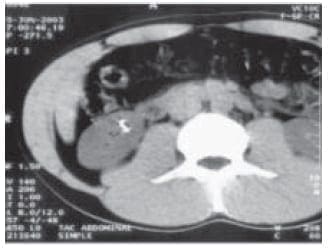

TAC abddominopélvico: Imagen intravesical hiperdensa con estructura metálica.

Se realiza cistolitotomía abierta sin complicaciones.

Lito de 6cm por 4cm. El análisis del cálculo comprobó la presencia de dispositivo intrauterino.